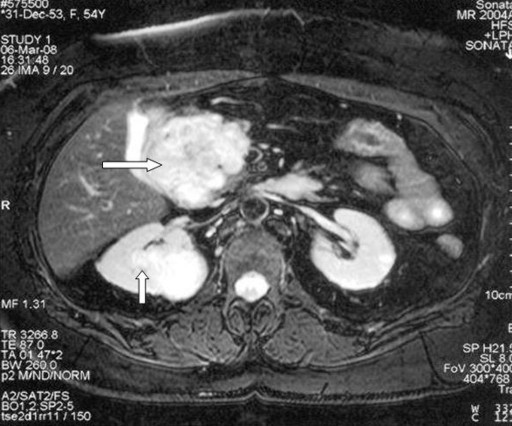

Investigation with abdominal ultrasound, CT scan and MRI with magnetic resonance cholangiopancreatography revealed two solid lesions on the right kidney, a 3.8 cm mass on the superior pole and a 1.2 cm mass on the inferior pole, both with the imaging characteristics of a renal cell carcinoma. Another 5 cm solid mass was found in the head of the pancreas, extensively compressing the antrum of the stomach and the duodenum as well as the inferior vena cava (Figure 1). The main pancreatic duct was significantly dilated and multiple cystic lesions of various sizes were also noted in the pancreatic body and tail (Figure 2). Upper GI endoscopy and endoscopic ultrasound revealed significant compression and a mucosal projection, without infiltration, on the posterior wall of the stomach and the second part of the duodenum, close to the ampulla of Vater which was caused by the pancreatic lesions. Endoscopic ultrasound-guided FNA biopsy of the lesion on the pancreatic head showed severe chronic pancreatitis. Pancreatic neuroendocrine hormones and urinary metanephrine excretion were within normal range. With a clinical diagnosis of von Hippel-Lindau disease, the patient underwent genetic evaluation which was positive for mutation R161P in exon 3 of the von Hippel-Lindau gene, in heterozygosis (direct sequencing).

Figure 1. MRI imaging. Right renal mass (vertical arrow) and solid mass in the pancreatic head (horizontal arrow) which proved to be a renal cell carcinoma and an atypical serous microcystic adenoma, respectively. |